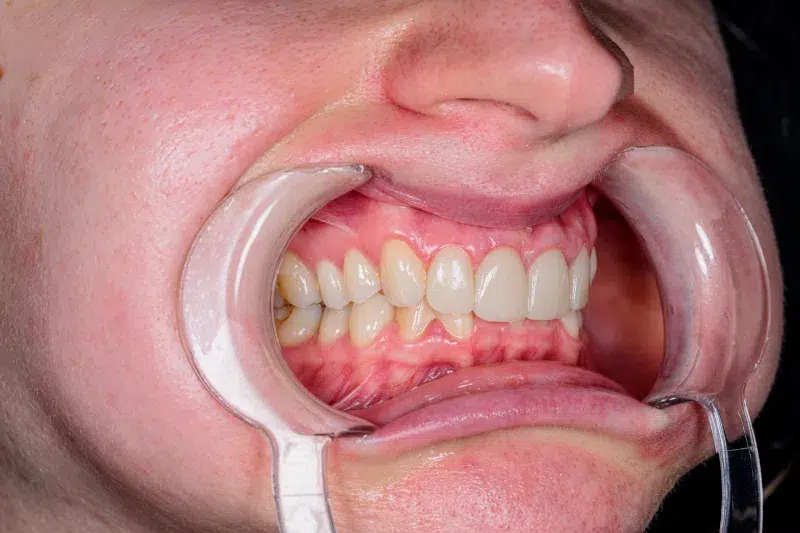

Caz estetică dentară – 4 coroane de zirconiu și ceramică E-Max

Provocarea acestui caz a fost în corectarea dinților laterali mult rotați prin aducerea lor la plan împreună cu incisivii centrali, pacienta refuzând purtarea unui aparat dentar.

Pacientă a beneficiat de corecție gingivala cu laser pentru asimetriile gingivale, tratamente endodontice de canal sub microscop, obturațiile vechi (plombe) schimbate cu materiale de compozit cu particule nanoceramice și 4 coroane de zirconiu ceramică.

Termen de finalizare 2 săptămâni de la amprentarea finală.